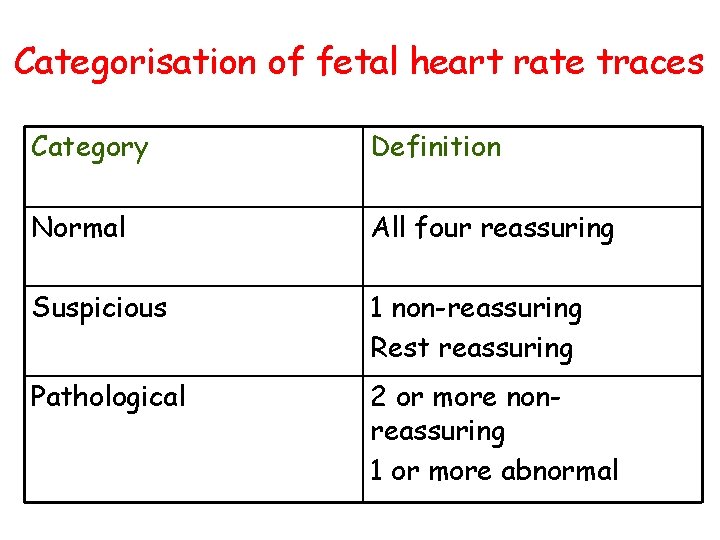

Cardio. Toco. Graphy • Normal • Suspicious • pathological

Categorisation of fetal heart rate traces Category Definition Normal All four reassuring Suspicious 1 non-reassuring Rest reassuring Pathological 2 or more nonreassuring 1 or more abnormal